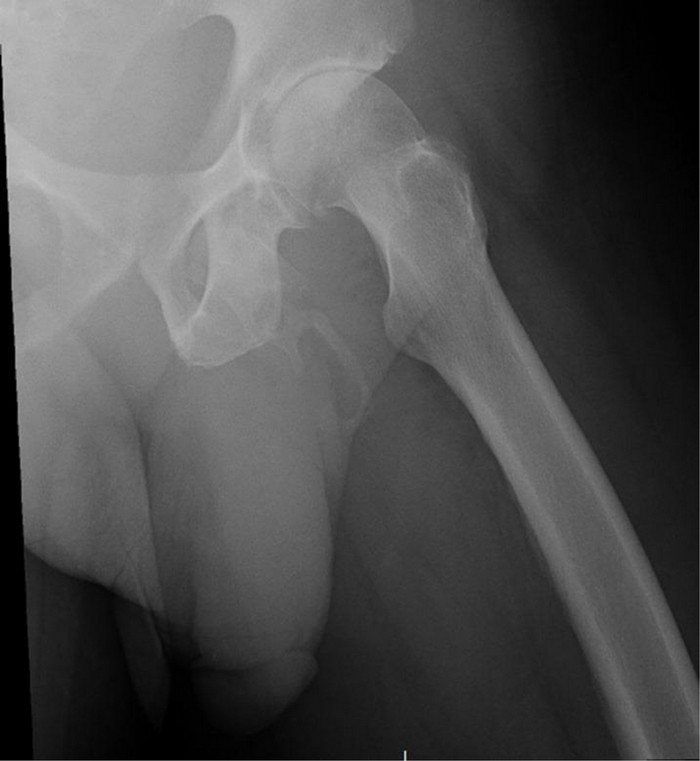

Georges El Hasbani of the American University of Beirut and his colleagues, explain the treatment of penis ossification in their case report, published in the journal Urology Case Reports. "The treatment of penis ossification depends on the extent of body ossification and the patient's symptoms."

![]() |

| Credits: Hasbani et al./Urology Case Reports, 2019 |

The case involving an uncomfortable acute pain or mild chronic pain can be managed with oral analgesics, topical agents, intralesional injections, mechanical stretching or vacuum devices, and extracorporeal shock wave therapy. Serious cases of extreme chronic pain or erectile dysfunction are usually treated surgically," they added.